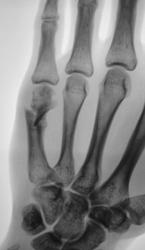

Катенёв Валенти... Дата публикации 02.12.2009, 22:30 Можно ли представленное рассматривать, как консолидированный перелом и выписывать пациента "к труду"? 1..VOPROS...JPG 2..VOPROS...JPG 3..VOPROS...JPG 4..VOPROS...JPG ВложениеРазмер 1..VOPROS...JPG71.9 КБ 2..VOPROS...JPG69.04 КБ 3..VOPROS...JPG77.01 КБ 4..VOPROS...JPG60.22 КБ Чт, 03/12/2009 - 14:39 #1 Глазков Игорь А... Не на сайте Был на сайте: 9 месяцев 2 недели назад Зарегистрирован: 19.12.2008 - 20:41 Публикации: 1597 определяется неправильно сросшийся субкапитальный перелом. Судить о возвращении к труду сложно, потому что , если труд физический, связанный с нагрузкой на кисть, то слабая костная мозоль может "дать трещину". Прийди к Себе Пт, 04/12/2009 - 18:35 #2 Vega Не на сайте Был на сайте: 3 месяцев 1 неделя назад Зарегистрирован: 22.01.2009 - 19:16 Публикации: 1087 Нет Пт, 04/12/2009 - 18:37 #3 Катенёв Валенти... Не на сайте Был на сайте: 7 лет 2 недели назад Зарегистрирован: 22.03.2008 - 22:15 Публикации: 54876 Спасибо Vega! Очень ждал, именно Вашего комментария. Еще раз большое спасибо.

определяется неправильно сросшийся субкапитальный перелом. Судить о возвращении к труду сложно, потому что , если труд физический, связанный с нагрузкой на кисть, то слабая костная мозоль может "дать трещину".